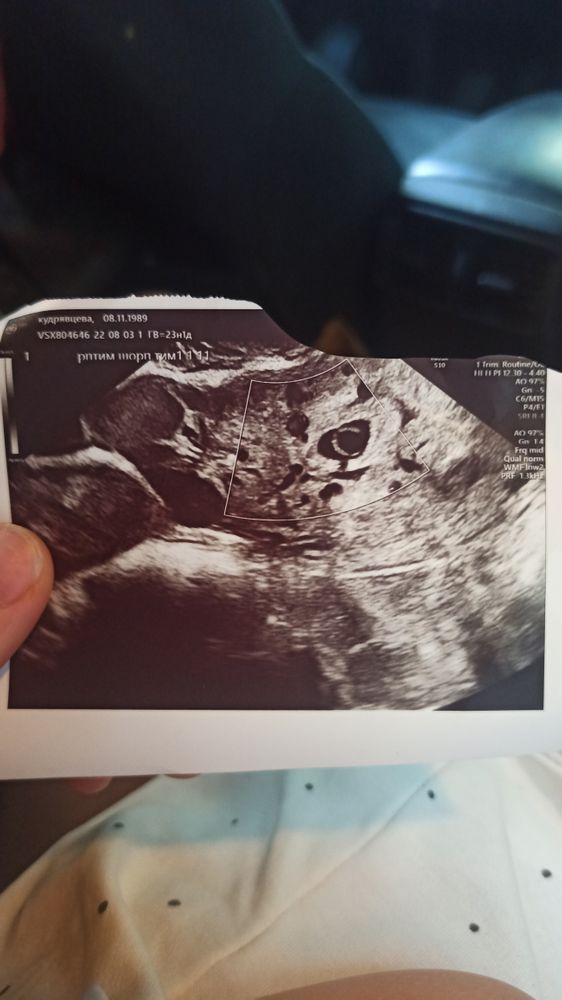

Изображение Вот фото УЗИ. Размеров не знаю.

Трудно судить по одному снимку. Надо видеть продольную и поперечную проекцию плодного яйца.

Ждите ещё неделю и потом опять УЗИ. Смотря какой ракурс, поэтому такое изображение. Возможно гематома немного давит на плодное яйцо, вот и такое изображение. Не забывайте что у вас была поздняя овуляция, поэтому срок некорректный